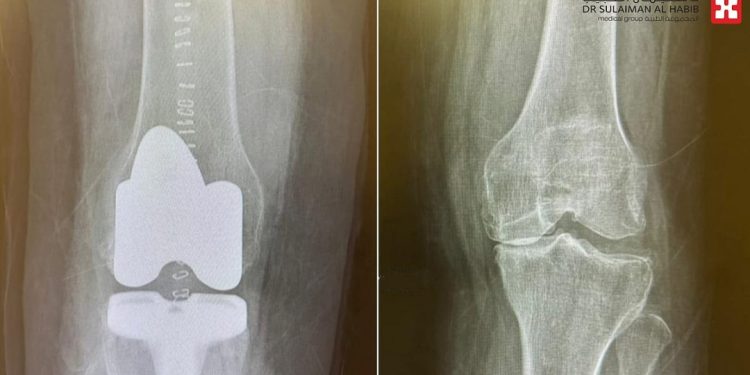

وأضاف أنه بعد مراجعة الملف الطبي وإجراء سلسلة من الفحوصات الدقيقة التي شملت الأشعة السينية الرقمية (Digital X-rays) والتحاليل المخبرية، تبيّن وجود خشونة متقدمة من الدرجة الرابعة في مفصلي الركبتين، بالإضافة إلى ميلان واضح في الساقين.

أُعدّت خطة علاجية شاملة، نُفّذت على مرحلتين، بدأت بـ استبدال مفصل الركبة اليسرى، تلتها عملية استبدال مفصل الركبة اليمنى، واستغرقت العمليتان نحو 120 دقيقة. وقد تكللت العمليتان، بفضل الله، بالنجاح التام دون أي مضاعفات.